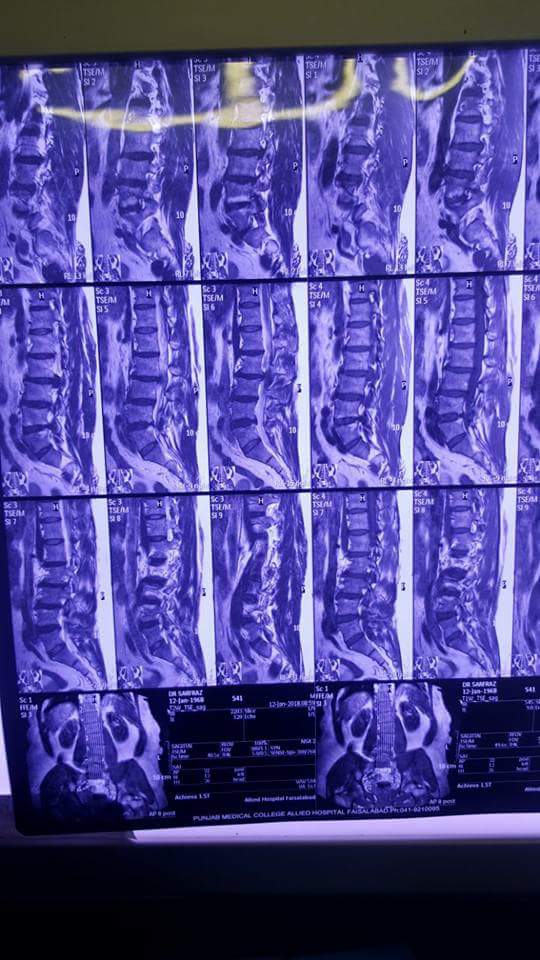

Lower back pain couple of years. Pain right thigh right knee joint. No recent trauma.

Thank you Dr sarfraz for asking. Although the radiographs and MRI are showing degenerative changes of spine and disc bulge as well, but a clinical examination is required. Cauda equina syndrome, characterized by loss of bladder or bowel function and saddle Anesthesia warrants emergency surgery. All other procedures are elective, depending on the clinical significant finding.

mri shows L3/4 disc prolapse.